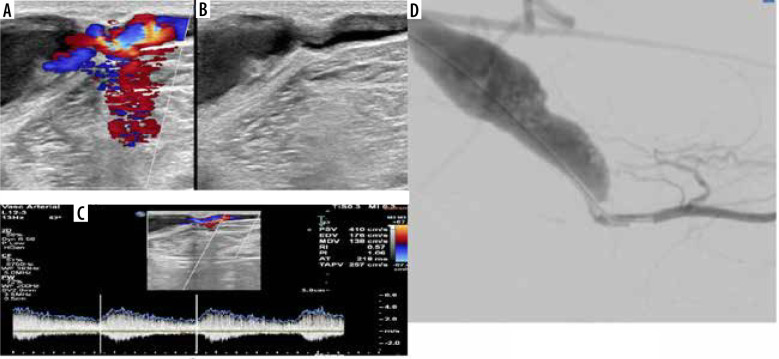

Results: Inter-observer agreement regarding complications of AVF/AVG was very good for the identification of thrombus (κ = 1.0), seroma (κ = 0.953), aneurysm (κ = 0.851), and pseudoaneurysm (κ = 0.851). It was considered good for the detection of juxta-anastomosis stenosis (κ = 0.751) and feeding artery stenosis (κ = 0.638). However, he agreement was fair for identifying draining vein stenosis (κ = 0.380) and distal arterial steal syndrome (κ = 0.210). The overall diagnostic performance of CDUS exhibited 86% sensitivity in identifying stenosis, with a specificity of 99.1%, a positive predictive value (PPV) of 96.5%, a negative predictive value (NPV) of 97%, and an accuracy of 94.3%.

Conclusions: CDUS is a noninvasive diagnostic approach for the prompt picking of AVF complications. It serves as a suitable first-line imaging modality for nonfunctional AVF due to its cost-effectiveness and accessibility. Additionally, we provide evidence of reproducibility, encouraging the diligent use of CDUS in AVF and AVG evaluation for early complication detection and management guidance.